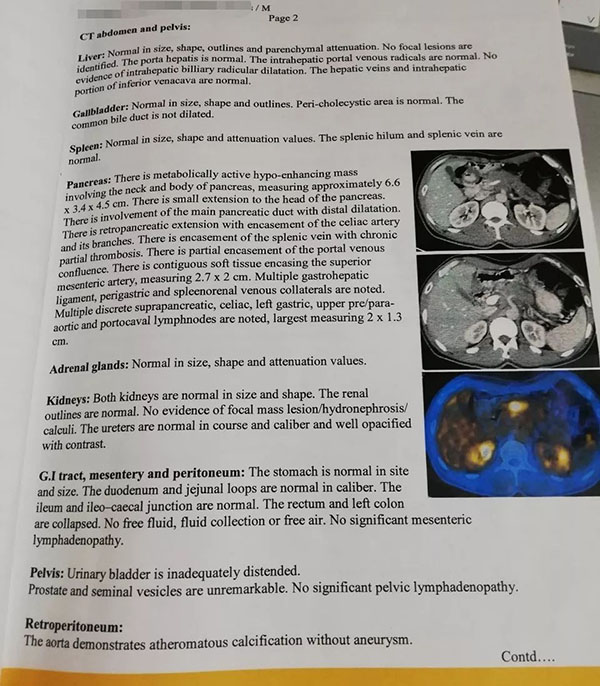

Before operation, CT showed that the pancreas was significantly larger, with an area of about 7 cm, and invaded the celiac trunk artery.

The operation process was very smooth, and the focus also showed obvious gray changes, which was a clear manifestation of tumor necrosis. After a few hours of rest in the ward, the patients recovered as normal and went home by themselves.